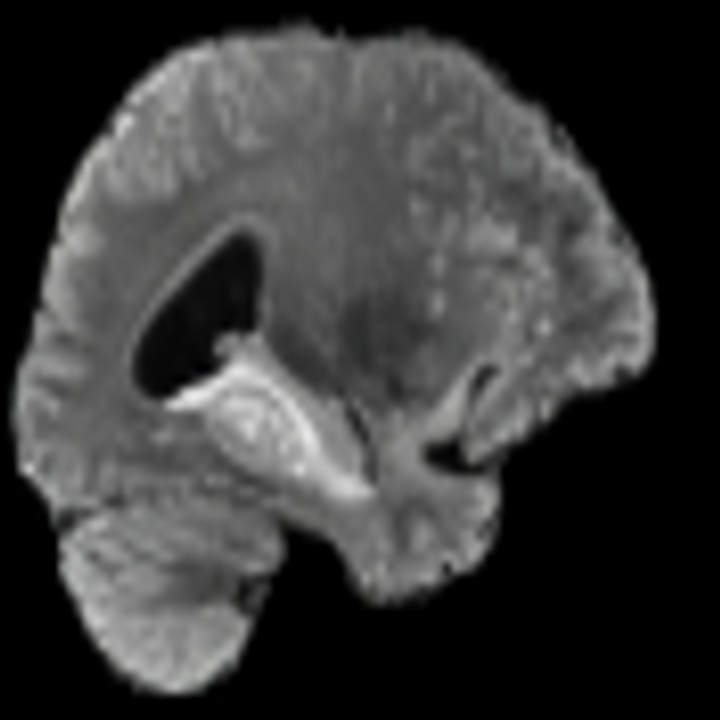

Tumour Information Preservation. For the brain tumor segmentation, we use a Swin UNETR model[28, 70], trained with random rotation, and intensity as data augmentation. On the test set with human ground-truth annotations (), the brain volumes generated from single slice input preserve the volume of the different tumour components (paired t-test, for all 3 classes). In Figure 4, we highlight the tumor profiles of the generated MRIs compared to the ground truth tumour profile. The real MRI Dice score in the test set is 85.15 while the generated MRIs from a single slice have a dice score of 83.09. This shows how the generated MRIs indeed preserve the tumor information and can act as an affordable and informative pseudo-MRI, before conducting an actual costly MRI examination in hospitals. More detailed results are provided in supplementary material.

Leveraging Context. Since we train on a predominantly cancerous brain dataset, one question that might arise is whether X-Diffusion generated MRIs preserve tumour information when the given inputs do not intersect with any tumour. We perform experiments varying the input slice index used to generate the 3D brain MRIs and measure the performance for input slices with no intersection with the tumour (not a single pixel with tumor label in the input slice). We also measure performance when only input slices are selected from tumor range. The Dice Scores of the random slices, no-tumour, and only-tumour are 83.09, 79.23, and 83.68 respectively. As can be seen here, the brain volumes generated from input slices with no tumour still preserve tumour information in reconstructed brain volumes despite a small drop in performance. This indicates that X-Diffusion is leveraging the context to preserve key information, such as tumor locations. This observation is consistent with how tumor segmentation models with global context [13] perform better than local-based U-Nets. More details are provided in supplementary material.